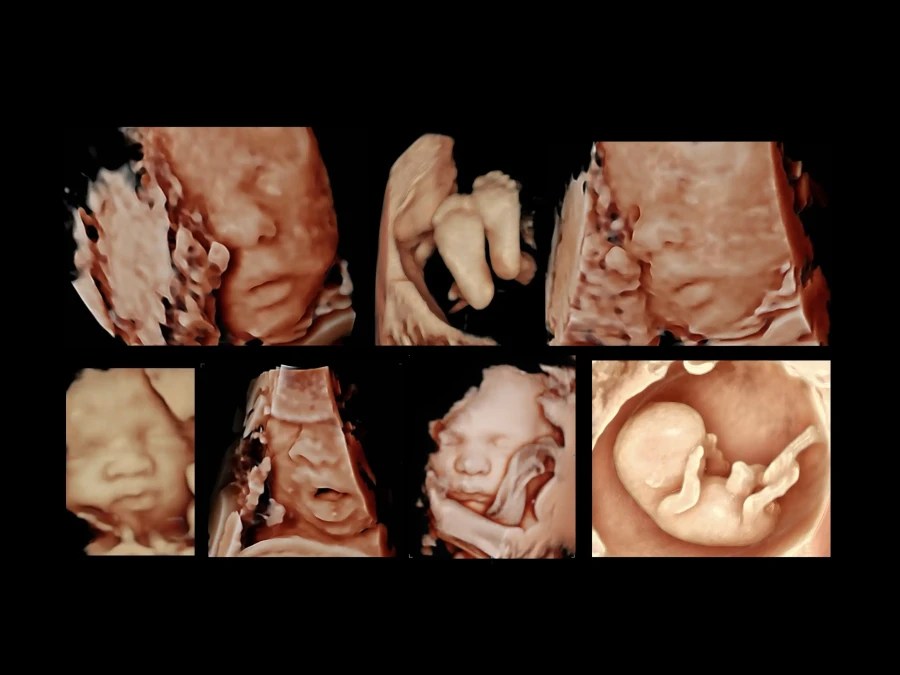

Υπερηχογραφήματα

3D / 4D υπερηχογράφημα εμβρύου